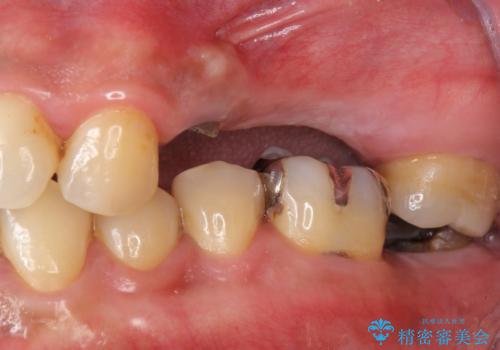

インプラント治療・セラミック治療を含む 全顎的虫歯治療

- 「 仕事が忙しく、虫歯を放置しすぎてしまった。この際全てきっちりと治したい。」と来院されました。

・歯の欠損

・虫歯

・深い虫歯

・欠損の放置による対合歯の挺出

・咬合平面の乱れ

・感染根管

以上のような問題を、徹底的な虫歯治療、歯周外科、インプラント治療、部分矯正治療、精密根管治療を用いてひとつずつ解決ししっかりと長期的に食事を楽しめるような口腔内環境の再構築を目指します。